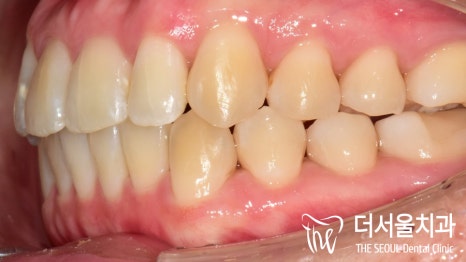

측면에서 바라보니,

앞으로 더 많이 뻐드러져 있는 것이 확인이 되죠?

이런 증세들 때문에

입술이 튀어나온 것 처럼 보여지게 되는 겁니다.

측면에서 바라봤을 때에도, 전과는 다르게

뻐드러짐이 없어진 것이 확인 됩니다.